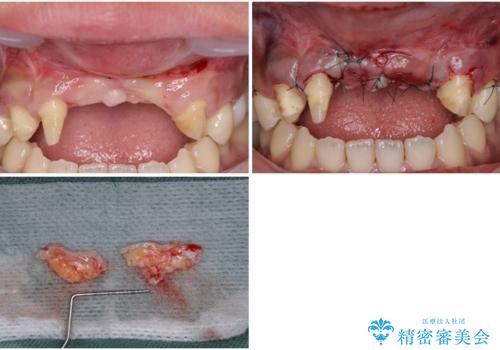

- ソーシャルメディアでのゲームに夢中になっている最中に車と接触し、前歯の抜歯を余儀なくされた患者様です。

初診時では前歯が保存できる可能性も模索しましたが、損傷が激しく3歯を抜去することとなりました。

保存となった隣在歯も神経が失活していており、補綴治療が必要であったので、オールセラミッククラウンにて補綴治療することとしました。

奥歯には元々欠損があり、欠損に伴う咬合不正も認められたため、部分矯正を行った上でインプラント補綴治療も行うこととしました。